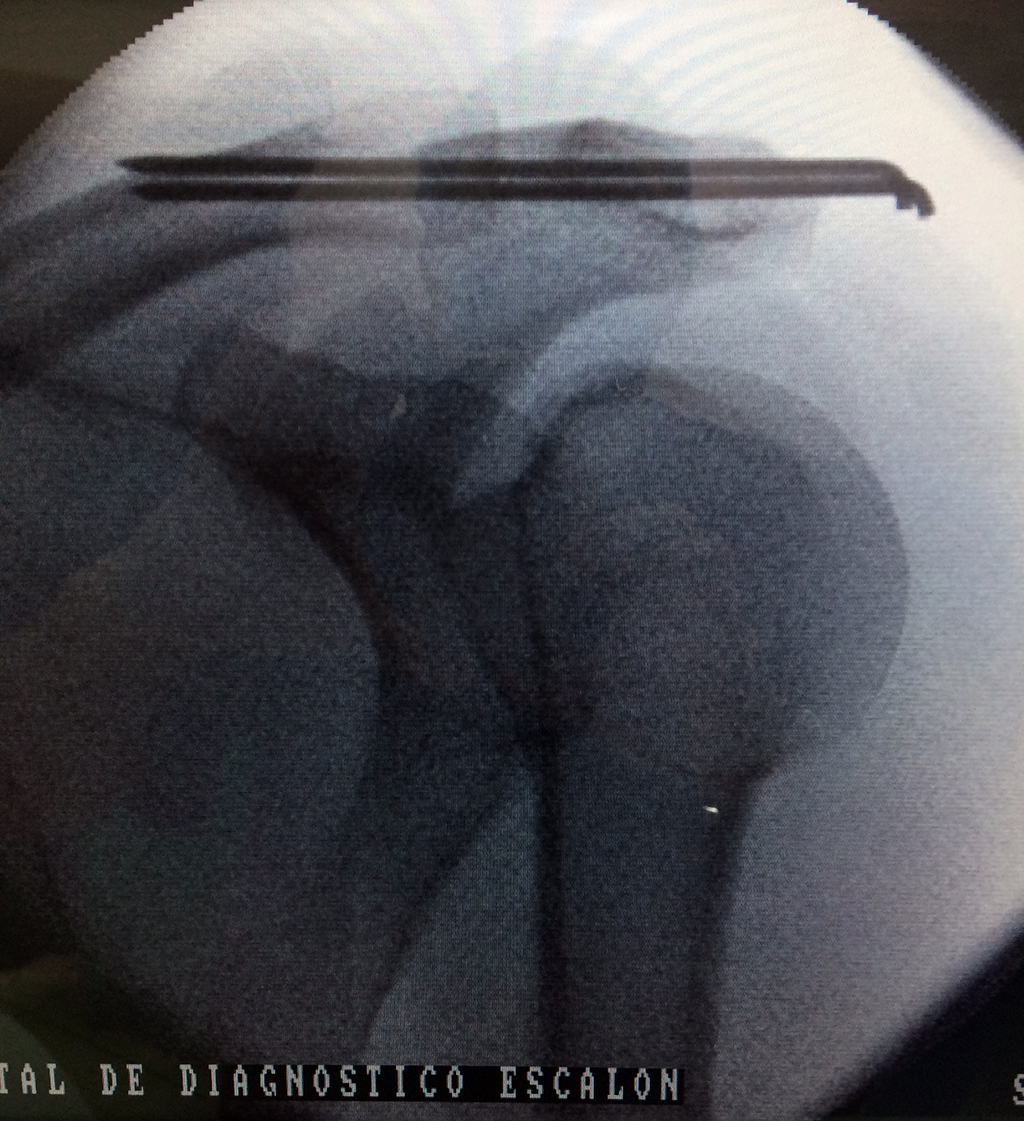

Fémur - Clavícula